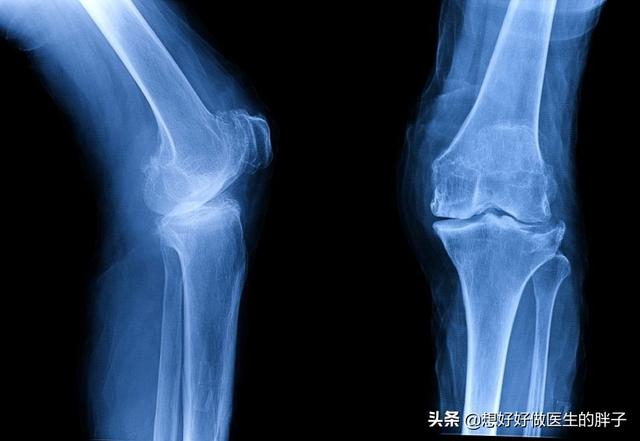

女性得骨关节炎的几率确实要比男性大的多,而且有研究表明,女性的骨关节炎对于患者影响的程度比男人还要重,临床上因为骨关节炎来看病的门诊患者,女性一般要比男性多3~4倍,尤其是膝关节骨关节炎!为什么会出现这种情况呢?主要是有以下的一些原因,今天正好有时间可以给大家详细的讲一讲:

这种下肢力线的异常会增加膝关节内侧关节软骨受到的压力,长此以往会导致软骨的退变,当退变达到一定程度的时候,患者就会出现膝关节的畸形,最常见的是膝内翻畸形,也就是我们常见的o型腿。